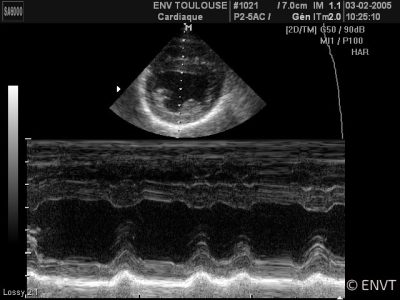

La cardiologie est la spécialité qui concerne l’état du coeur et du système vasculaire de l’animal. Les examens effectués au sein du service ont pour but de prévenir, diagnostiquer ou traiter des maladies cardiaques, vasculaires ou respiratoires.

Les consultations sont réalisées pour les chiens, chats, et NAC, que ce soit pour le diagnostic, le suivi ou le dépistage de cardiopathies (affections cardiaques) congénitales (présentes à la naissance) ou acquises (exprimées à l’âge adulte).